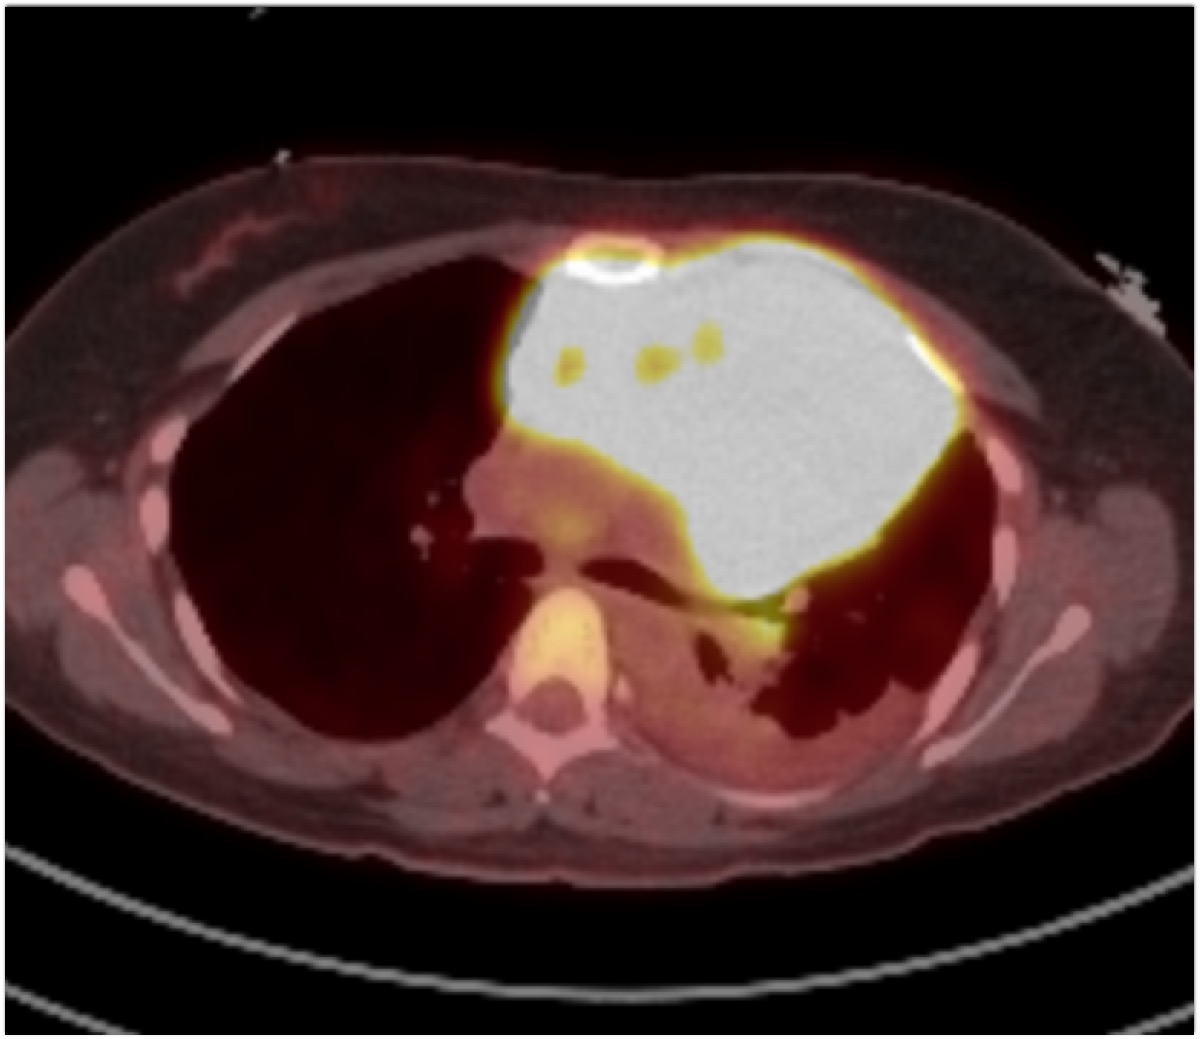

The most likely diagnosis in this 30ish year old with FUO is?

teratoma

thymoma

ectopic thyroid tissue

B-cell lymphoma